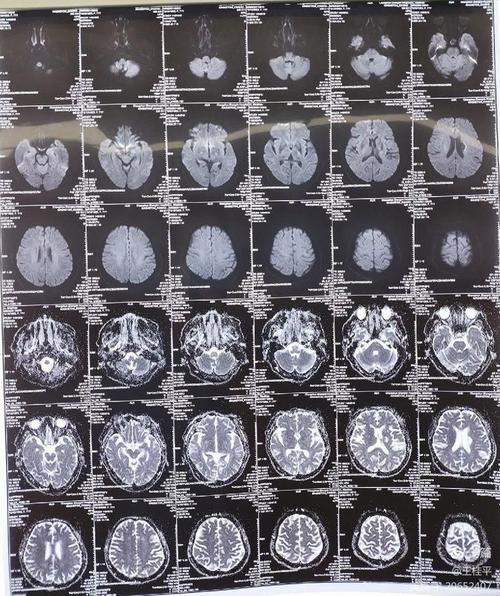

“右边脑梗一年后左边脑梗”意味着患者在大脑右侧发生了一次脑梗塞,经过一年时间后,大脑的左侧又发生了新的梗塞,这被称为复发性脑卒中。

这表明患者脑梗塞的根本原因可能没有得到有效控制,或者存在新的诱因,复发性脑梗的病情往往比首次更严重,致残率、致死率都更高,因此必须引起高度重视。

- 全面检查:入院后,医生会安排头颅CT/MRI、颈部血管超声/CTA/MRA、心脏超声、血液化验(凝血功能、血脂、血糖等)等一系列检查,以明确这次梗塞的原因、位置和范围,并评估全身状况。